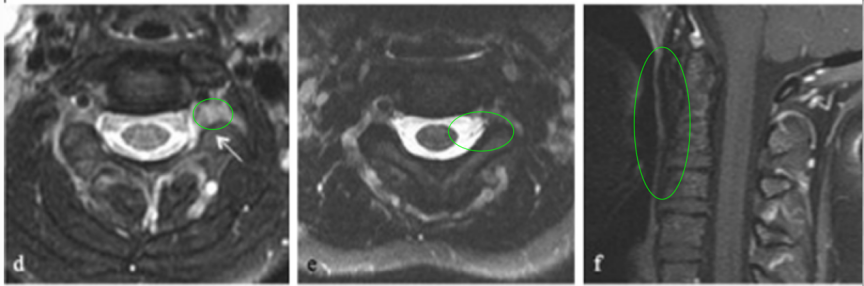

10岁患儿临床表现为头晕颈痛、复发性咽喉感染和吞咽困难,确诊C1-C3脊索瘤伴上呼吸道压迫。经详细评估后,行经口、经腭、经下颌入路次全切除术。

术后影像显示C2-C3神经孔残留病变,遂制定个性化放疗方案。患儿对70Gy光子放疗反应良好,耐受性佳,残留病变明显缩小且无显著放疗副作用。

据文献报道(1973-2014年808例原发性脊索瘤数据),脊索瘤5年生存率达68.4%,10年生存率为39.2%。该病例随访10年无复发,未出现神经功能缺陷,验证了综合治疗方案的长期有效性。